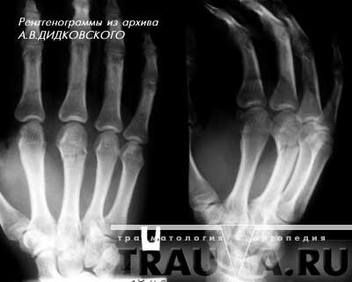

Рисунок 5 - Перелом основания средней фаланги 3 пальца кисти со смещением остеосинтез спицами.

Необходимое лечение переломов пальцев: Непременно следует добиться сопоставления отломков. Это необходимо для того, чтобы избежать утраты функции пальца. Если случился перелом без смещения, следует наложить на поврежденный палец ладонную гипсовую лонгету либо шину Белера. Делается это, как правило, примерно на один месяц. Если консервативным путем сопоставить отломки невозможно, тогда производят оперативное лечение. Специалисты обнажают отломки, а затем фиксируют одной или двумя спицами и костным штифтом, после этого накладывают гипсовую повязку сроком на один месяц. Порой используют скелетное вытяжение за ногтевую фалангу. Вскоре после того, как наложат гипс или произведут оперативное лечение, рекомендуется производить движения соседними пальцами (11, с.56).